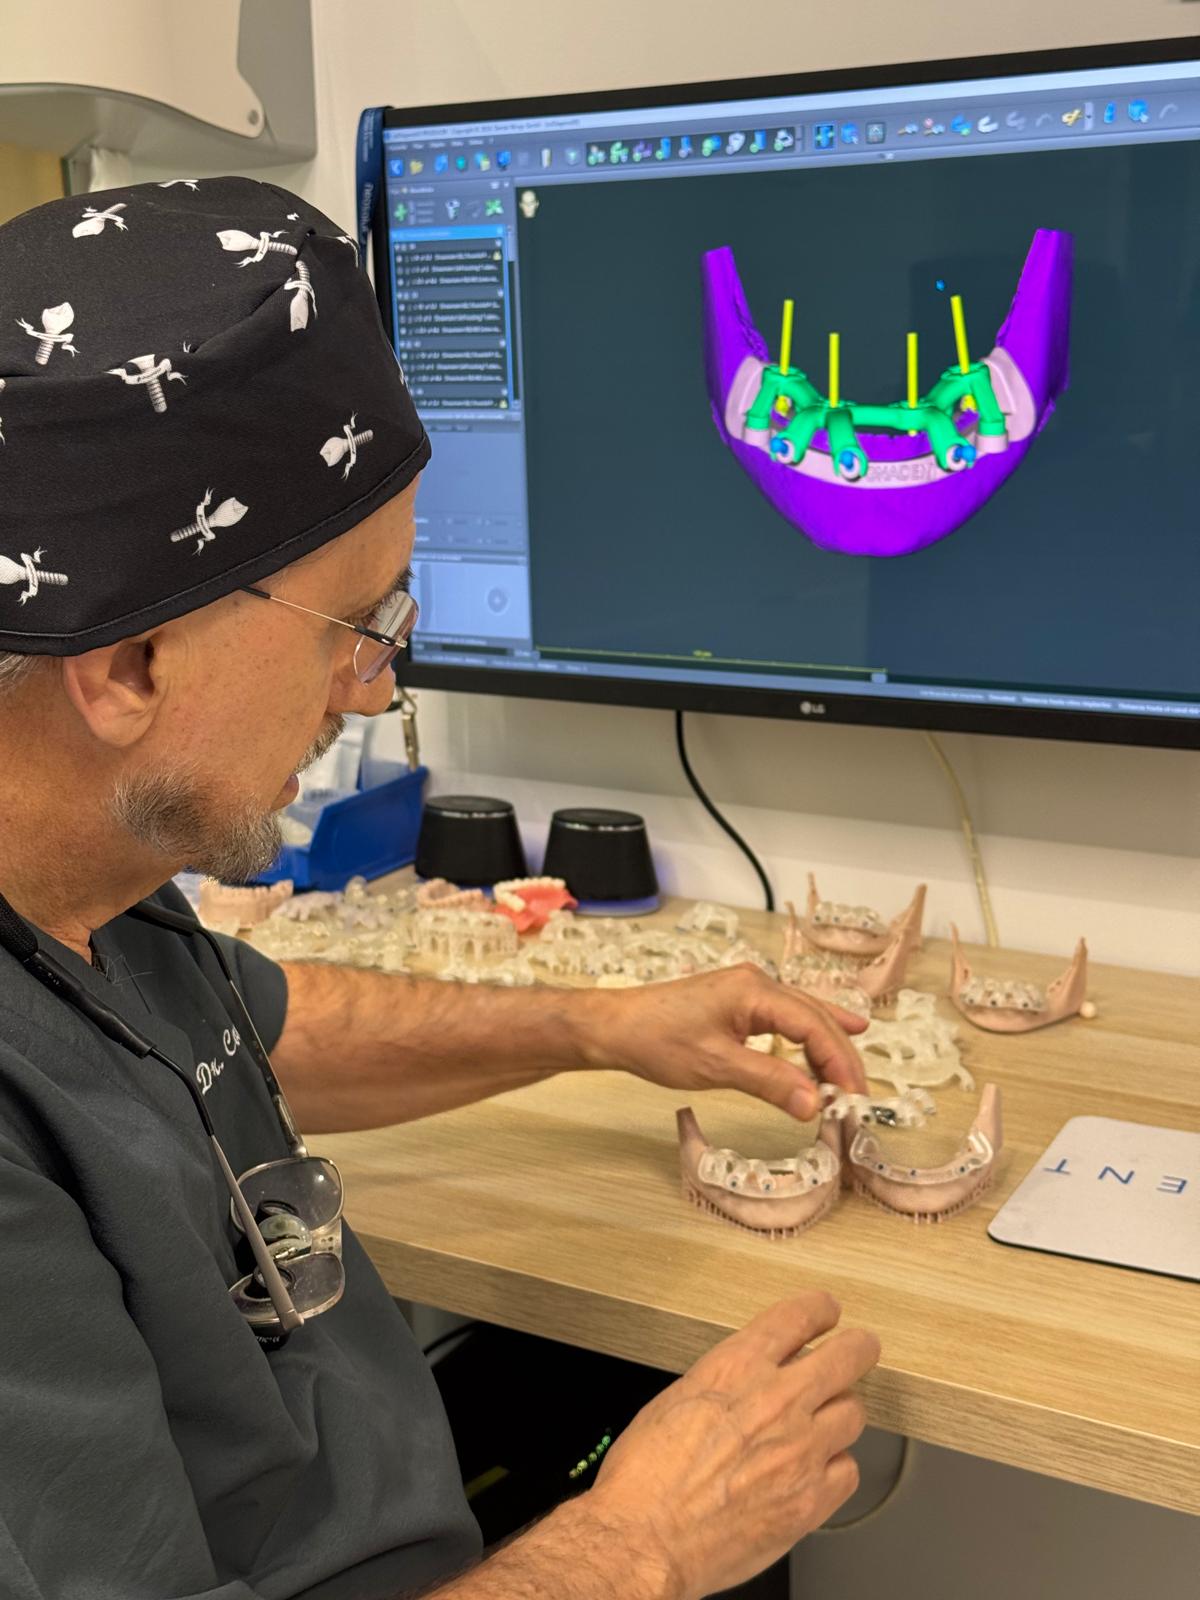

Protocolo de Precisión Digital

Hemos eliminado la improvisación. Cada paso de tu tratamiento está digitalizado para maximizar la seguridad, reducir tiempos y mejorar tu confort.

Diagnóstico y Escáner 3D

Realizado por el Dr. Company o la Dra. Chuliá. Te entregamos un plan de tratamiento completo y digitalizado, sin compromisos.

Planificación Digital

Analizamos tu caso en software 3D antes de tocarte. Diseñamos la posición exacta de cada implante o carilla para garantizar la estética y función perfectas.

Cirugía Guiada

Gracias a la impresión 3D de férulas quirúrgicas, colocamos los implantes en la posición exacta planificada. Mínimamente invasivo, a menudo sin puntos de sutura.

Cuando el deterioro es avanzado, los parches no funcionan. Necesitas una reconstrucción desde los cimientos. El Dr. Fernando Company lidera una planificación multidisciplinar donde periodoncia, implantología y estética se unen mediante protocolos integrales para recuperar función y estética en casos de desgaste severo y pérdida de varias piezas dentales.

El Dr. Company supervisa personalmente cada fase de tu tratamiento.